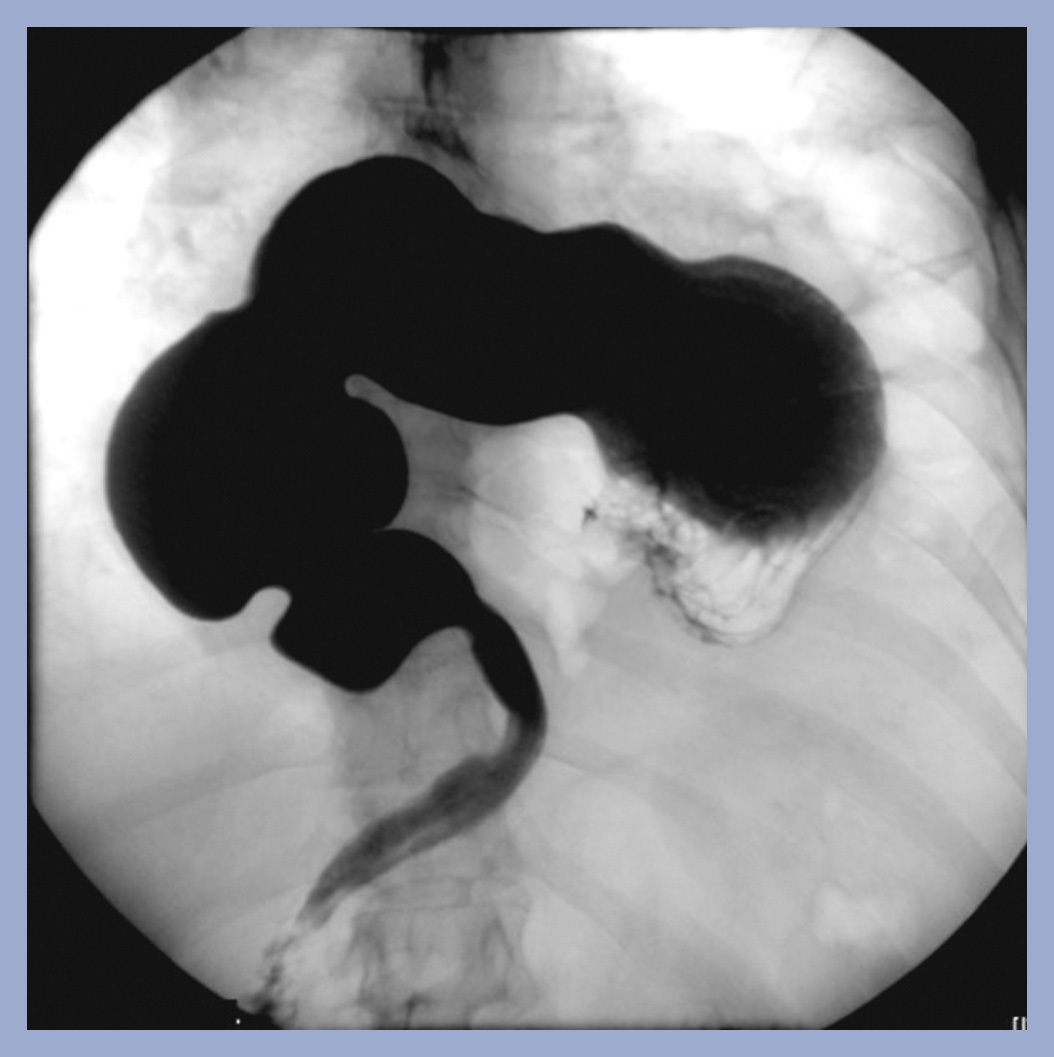

What is going on in this spot fluoroscopic film?

This is organoaxial volvulus of the stomach. It is most likely due to a large hiatal hernia into the chest (type IV hiatal hernia).

It produces an ‘upside-down’ apperance of the normal anatomy. These patients will typically present with epigatric/chest pain and vomiting.